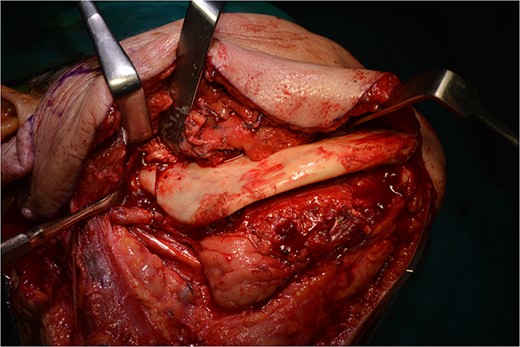

Operatively, after induction to general anaesthesia via orotracheal intubation, an extended submandibular incision to the right of the neck was performed and the mandible was revealed. The marginal branch of the facial nerve was recognized and protected. Following this, the double osteotomy of the mandible was performed in the parasymphysis—with preplating of two miniplates with four holes—and in the subcondylar area—with preplating of two miniplates with four holes (Figs 3 and 4). The mandibular ‘swing’ that was performed straight after that (Fig. 5) gave space for the dissection of the CCA and the bifurcation. All the branches were prepared, and the aneurysm was accessed (Fig. 6). The reconstruction was achieved by bypassing the aneurysm, trans-positioning of the right ECA and end-to-end anastomosis of the ECA with the healthy peripheral end of the ICA near the skull base, after the lignification of the peripheral end of the ECA and its smaller branches (Fig. 7). The anastomoses were checked for leakage (Fig. 8), the mandible was reduced and the easily fixated rigidly after preplating (Fig. 9).

The step before the end-to-end anastomosis of the external carotid artery with the healthy peripheral end of the internal carotid near to the skull base.